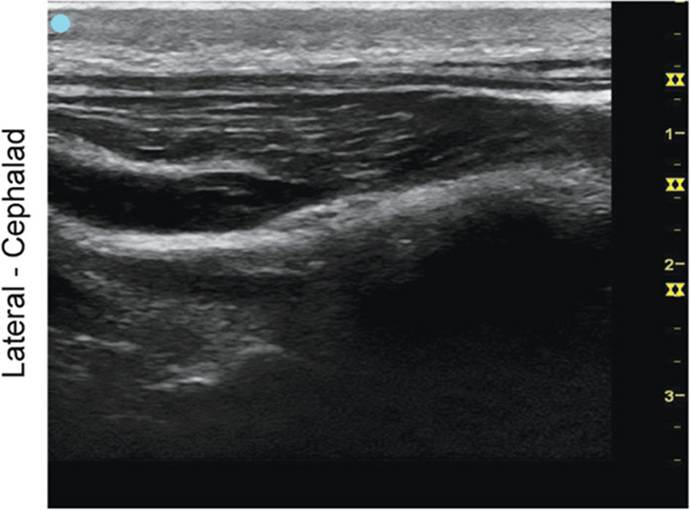

Greater Occipital Nerve, Longitudinal View

FIGURE 7.1.2A Ultrasound transducer position to image the greater occipital nerve, longitudinal view.

FIGURE 7.1.2B Ultrasound image of greater occipital nerve, longitudinal view.

FIGURE 7.1.2C Labeled ultrasound image of greater occipital nerve, longitudinal view.

Abbreviations: TrM, Trapezius Muscle; SsCM, Semispinalis Capitis Muscle; IObCM, Inferior Oblique Capitis Muscle; GON, Greater Occipital Nerve; LsCM, Longissimus Capitis Muscle.